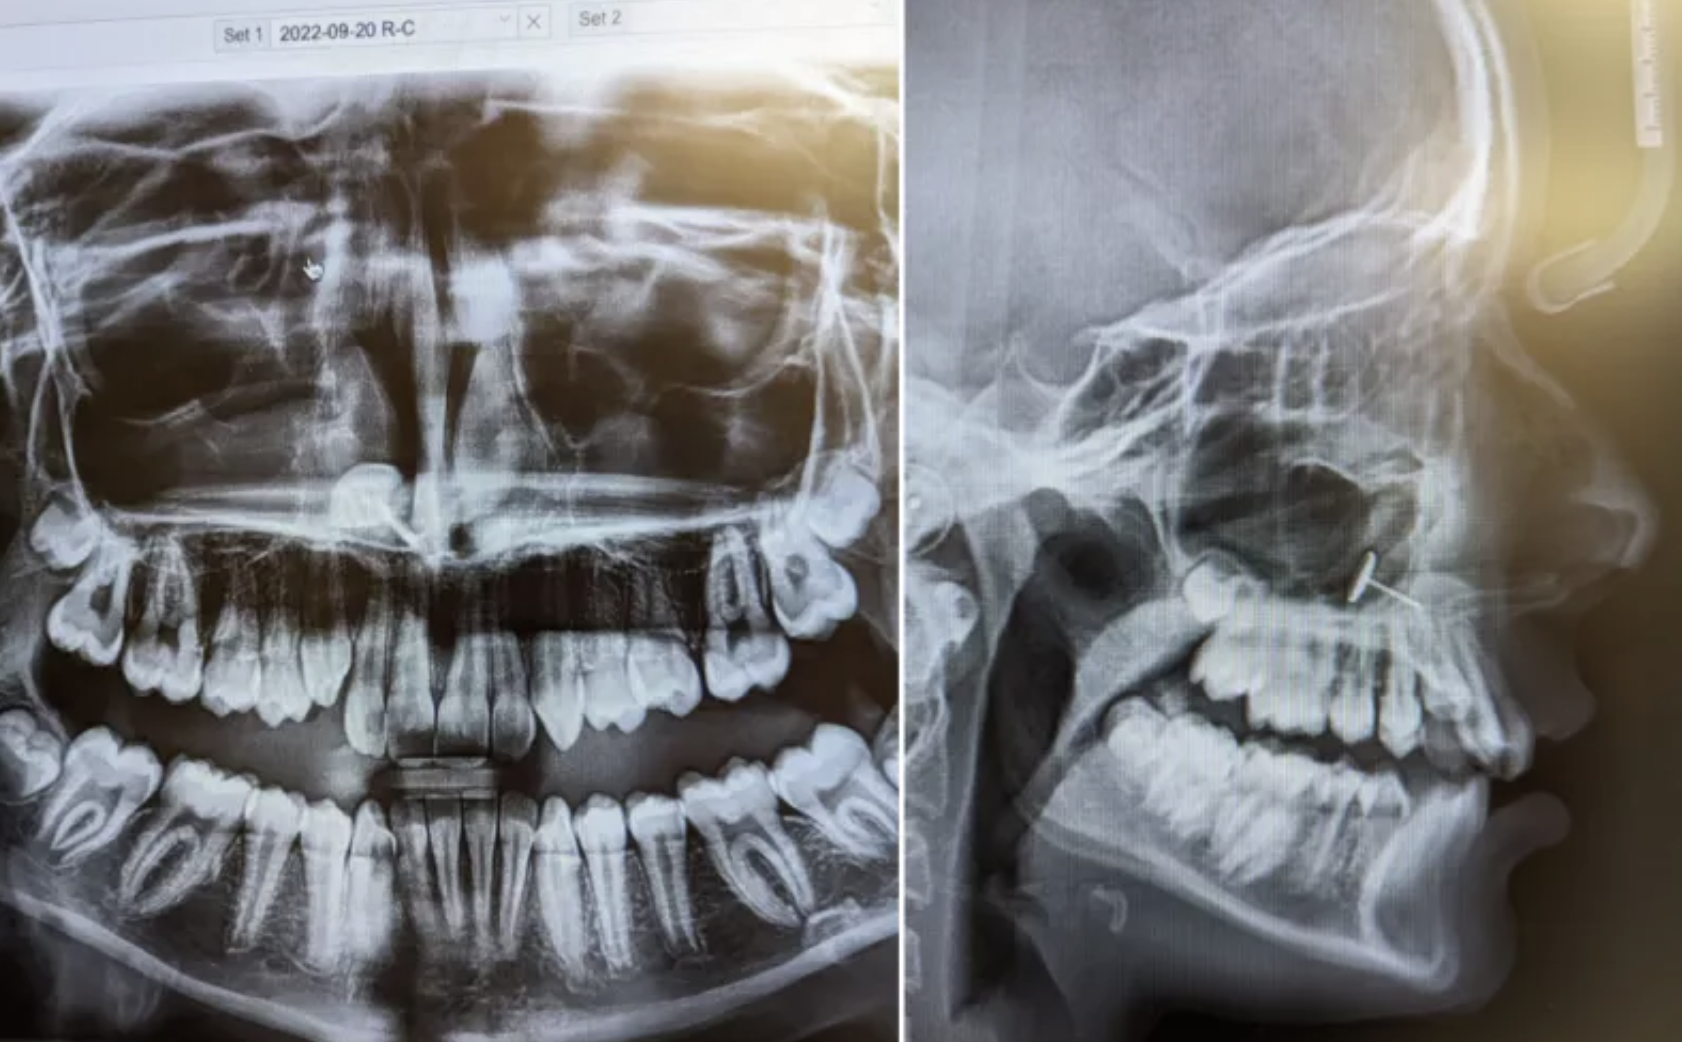

Мама привела доньку на рентген зубів і була шокована тим, що знайшли в роті дитини (фото)

Візит до стоматолога набув неочікуваного повороту для матері та доньки зі штату Вашингтон, США. Жінка повела свою 13-річну доньку до ортодонта, щоб розпочати процес встановлення брекетів, але вона ніколи не могла передбачити, що покаже рентгенівський знімок рота її дитини.

Лікар повернувся до кімнати та показав рентгенівські знімки на екрані. Усі в приміщенні побачили "це" одночасно та кілька хвилин намагалися зрозуміти, що вони бачать. Про це пише Newsweek.

Те, на що вони дивилися, здавалося, був невеликий шматочок металу, який застряг у пазухах підлітка. Жінка не могла пояснити, як він туди потрапив, але одна людина в кімнаті точно знала, що сталося: її донька.

"Схоже, в якийсь момент вона вирішила спробувати проштовхнути сережку зсередини. Я не впевнена, чи вона чхнула, чи що сталося, але зрештою вона вдихнула сережку. Вона застрягла в її пазухах", — каже мама пацієнтки.